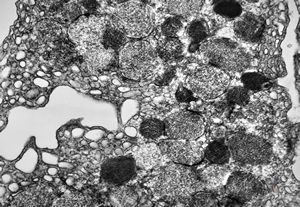

F, 24y. | molluscum contagiosum … virions